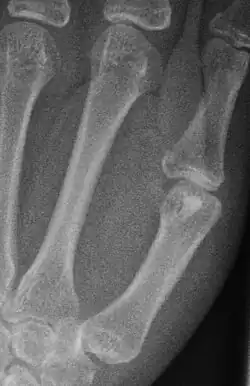

Enostom im Köpfchen ersten Mittelhandknochens

Das Enostom, auch Kompaktainsel, Enosteom oder engl. bone island genannt, ist eine Insel kortikalen Knochens im Markraum, in der Regel eines Röhrenknochens. Das Enostom ist ein häufiger, gutartiger Nebenbefund und stellt sich als meist ovoide oder runde Zone vermehrter Dichte (Sklerosierung) dar. In der Skelettszintigrafie ist dieser Befund negativ und kann so von osteoplastischen (knochenbildenden) Knochenmetastasen unterschieden werden.